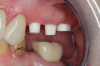

Fig 18. Preoperative image.

Figure 18

Occasionally dentists are presented with extreme challenges with long-term restorations and replacing missing teeth. Dentists must evaluate the patient's condition, develop optimum long-term oral health, and attempt to meet the patient's expectations. Figure 18 showed a class III malocclusion with deep bite, multiple abfractions, and less-than-ideal occlusal plane, but the patient wanted to replace his maxillary right canine only. A discussion with the patient regarding occlusal disharmonies and comprehensive recommendations for full-mouth rehabilitation revealed that the patient had a limited budget for dental care. The patient understood the ramifications of his comprehensive dental needs not being affordable. Decisions were made to atraumatically remove the maxillary right canine (Figure 19) and immediately place a ceramic dental implant (Figure 20). Polytetrafluoroethylene (PTFE) 4-0 sutures were placed to help support soft tissues, and then a full-arch Essix-style retainer with a flowable composite facial veneer was used to provide some esthetics during the patient's healing phase (Figure 21). The implant and the retainer were not to be in contactthe retainer may occlude with the opposing dentition and also be passive in relation to the ceramic implant.